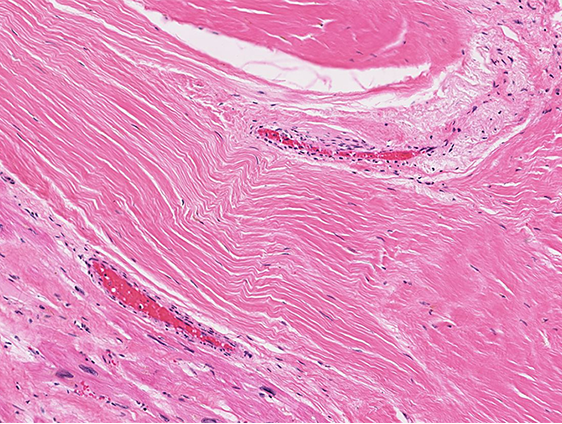

Constitutively Active Repair:

Sometimes the signals that cause repair to progress to mature scar become stuck in the "on" position

Examples of this include excessive granulation tissue ("proud flesh"), keloid scars, and idiopathic pulmonary fibrosis

Do the following image represent up- or downregulated repair?